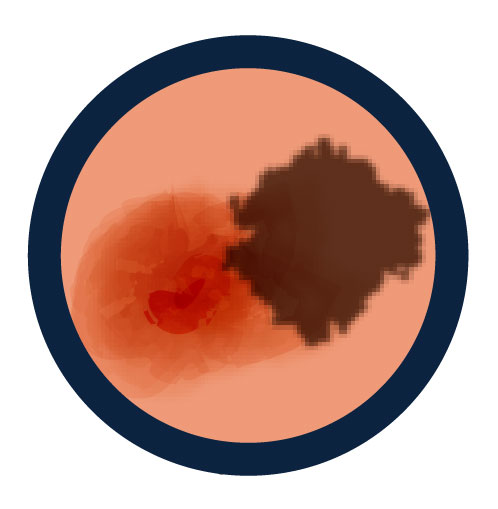

A is for Asymmetry

One half of a mole or birthmark does not match the other.

B is for Border

The edges are irregular, ragged, notched or blurred.

C is for Color

The color is not the same all over and may include different shades of brown or black, or sometimes with patches of pink, red, white, or blue.

D is for Diameter

The spot is more than 6 millimeters across (about 1/4 inch – the size of a pencil eraser), although melanomas can sometimes be smaller than this.

E is for Evolving

The mole is changing in size, shape, or color.